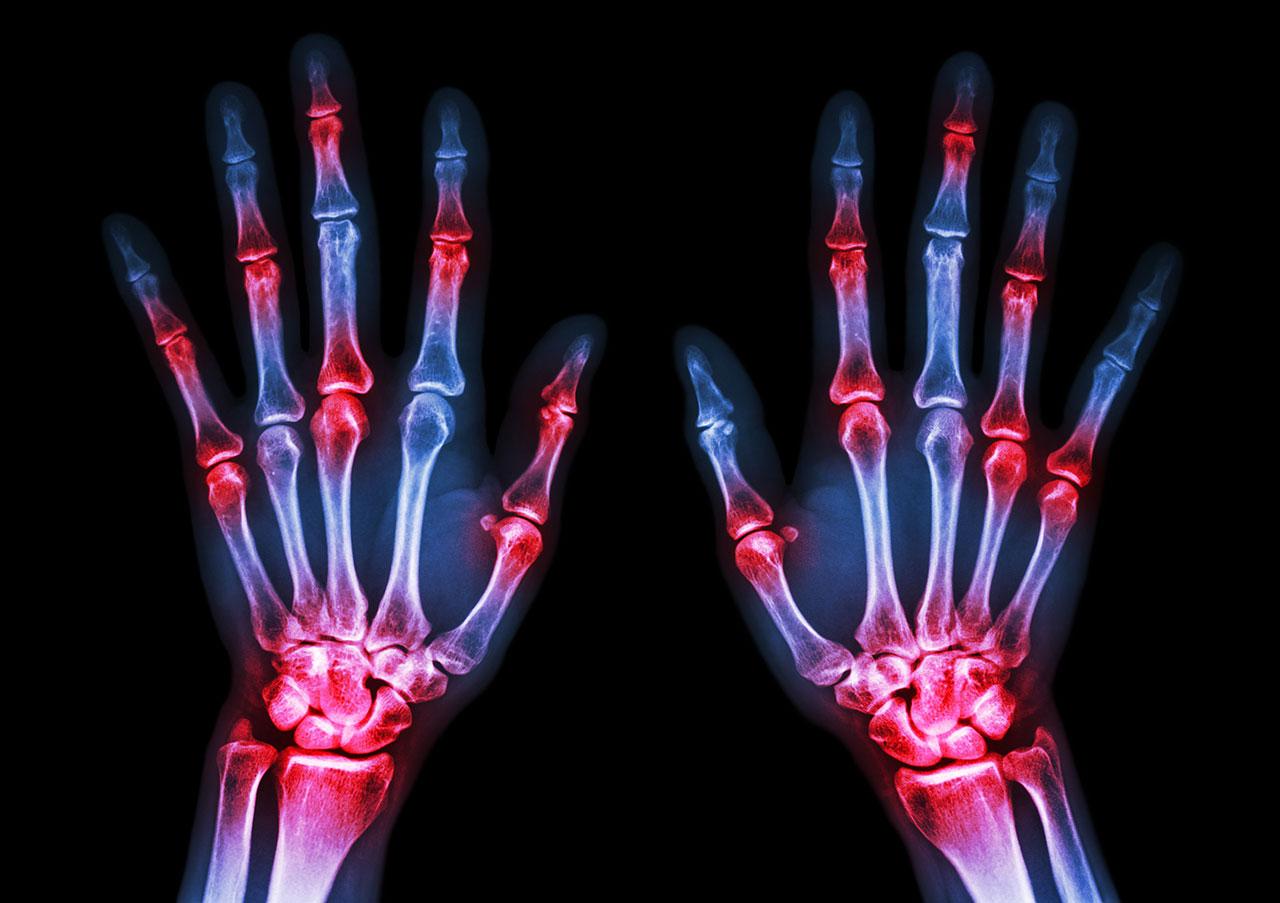

อาการที่สำคัญของผู้ป่วยโรคเกาต์คือ ข้ออักเสบเฉียบพลัน ผู้ป่วยจะมีอาการปวด บวม แดงร้อนที่ข้ออย่างชัดเจน ในบางรายอาจมีไข้หรือมีอาการหนาวสั่นร่วมด้วย โดยประมาณร้อยละ 80 พบว่าข้ออักเสบเฉียบพลันครั้งแรกจากเกาต์มักเป็นข้ออักเสบข้อเดียว ข้อที่พบบ่อยคือ ข้อโคนนิ้วหัวแม่โป้งเท้า ข้อเท้า ข้อเข่า ผู้ป่วยบางคนจะมีอาการปวดทรมานมาก ปวดจนไม่สามารถลงน้ำหนักบริเวณข้อได้ บางคนถึงขั้นต้องนั่งรถเข็นมาพบแพทย์ อาการปวดจะปวดแบบเฉียบพลัน คือ เริ่มปวดจนถึงมีอาการปวดสูงสุดใน 1 วัน หลังจากนั้นประมาณ 3-10 วันอาการข้ออักเสบก็จะหายไป โดยผู้ป่วยบางรายอาจจะให้ประวัติมีปัจจัยบางอย่างที่กระตุ้นให้เกิดข้ออักเสบ เช่น ดื่มสุรา รับประทานอาหารที่มีพิวรีนสูงเป็นปริมาณมาก หรือได้รับอุบัติเหตุบริเวณข้อนั้น เป็นต้น

ในระยะแรกๆ ของโรค อาการข้ออักเสบของผู้ป่วยมักจะเป็นไม่บ่อย เป็นเพียงปีละ 1-2 ครั้ง แต่ถ้าปล่อยให้กรดยูริกในร่างกายสูงเป็นระยะเวลานาน และไม่ได้รับการรักษาที่ถูกต้อง จะมีข้ออักเสบเฉียบพลันกำเริบบ่อยขึ้น เป็นนานขึ้น หายช้าลง และจะเริ่มลามมีที่บริเวณข้อส่วนบนของร่างกาย เช่น ข้อนิ้วมือ ข้อมือ ข้อศอก เป็นต้น และอาจจะมีข้ออักเสบเกิดขึ้นพร้อมกันหลายข้อได้ นอกจากนี้หากปล่อยทิ้งไว้เป็นระยะเวลานาน จะทำให้มีการตกตะกอนของผลึกเกลือยูเรตตามเนื้อเยื่อต่างๆ ในระยะแรกผลึกจะสะสมในเยื่อบุข้อ และต่อมาจะสะสมบริเวณรอบๆ ข้อ รวมไปถึงใต้ผิวหนัง ทำให้เกิดกลุ่มก้อนหรือปุ่มใต้ผิวหนัง เรียกว่าก้อนโทฟัส พบได้บ่อยที่นิ้วเท้า หลังเท้า ตาตุ่ม เอ็นร้อยหวาย ข้อศอก นิ้วมือ หลังมือ รวมไปถึงใบหู ซึ่งส่งผลเสียต่อบุคลิกภาพ ในบางครั้งก้อนโทฟัสเหล่านี้อาจแตกออกมาเป็นผงคล้ายชอล์ค ทำให้เกิดแผลเรื้อรังตามมา เกิดการติดเชื้อแบคทีเรียซ้ำซ้อนได้ นอกจากนี้ก้อนโทฟัสเหล่านี้ยังสามารถกัดกร่อนกระดูก ทำให้เกิดข้ออักเสบเรื้อรัง ส่งผลทำให้ข้อผิดรูป เกิดภาวะทุพพลภาพตามมา